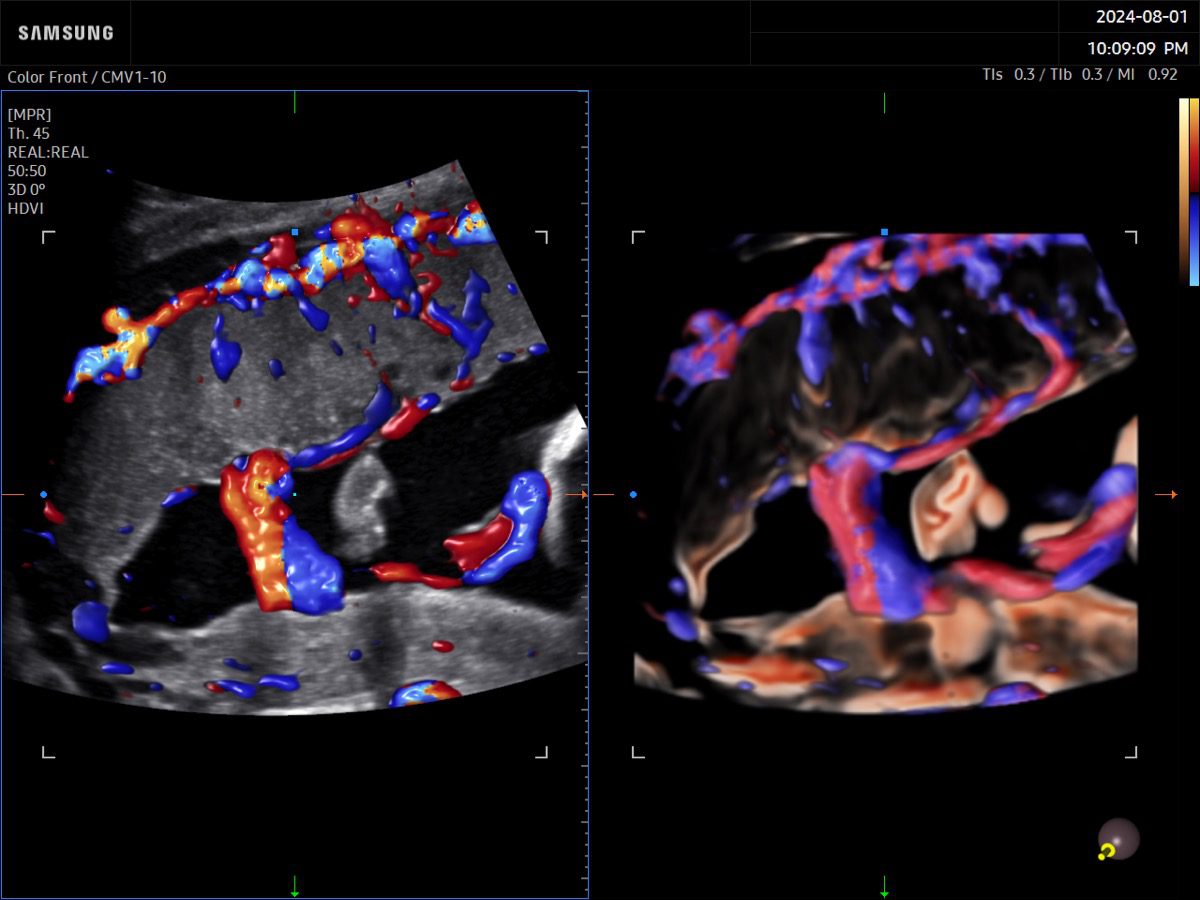

Procedural Services

Comprehensive, advanced and expert MFM care for high-risk pregnancies

- Fetal anomalies